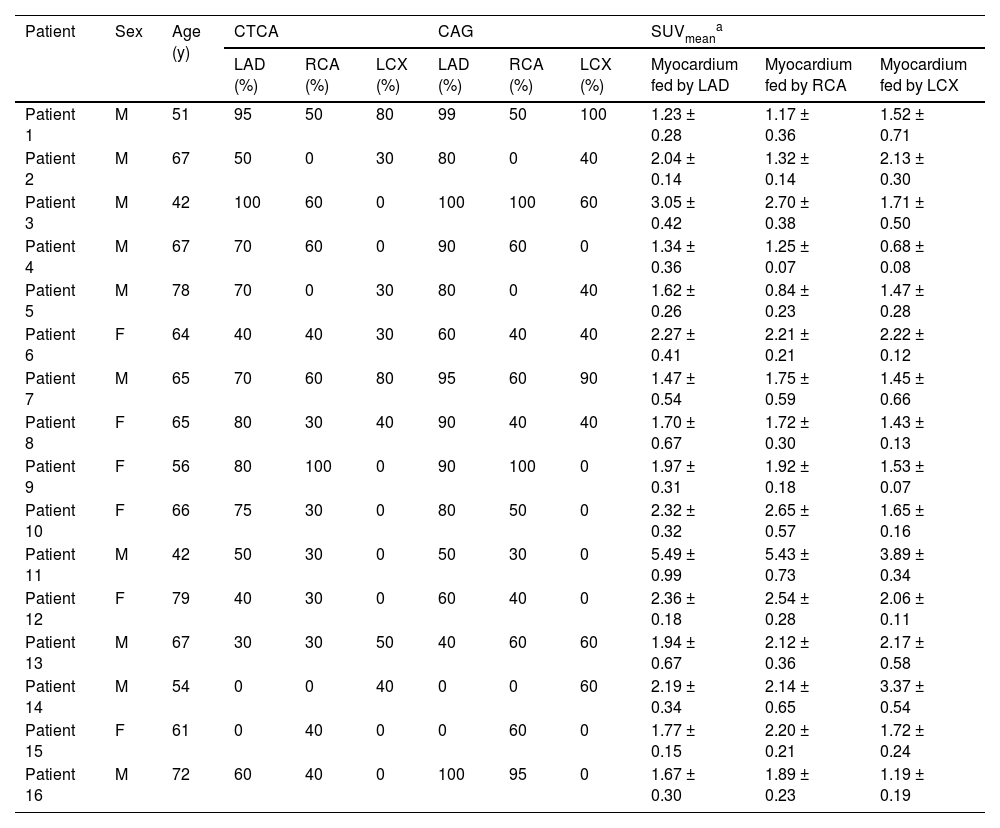

Distributions of FAPI uptake in patients with CADThe LV myocardial wall was divided into three parts based on the blood-supplying areas of the main coronary arteries, LAD, RCA, and LCX areas, which are shown in the polar maps from the short-axis view of the cardiac PET images (Fig. 3). Myocardial regions supplied by coronary arteries diagnosed as stenotic by CTA exhibited abnormally high FAPI uptake. Moreover, FAPI-uptake was significantly higher in areas supplied by the occluded coronary artery than in those with normal blood supply in the same CAD patients (all p-values ˂ 0.05; Fig. 4A and Table 2).

Representative images in participants with coronary stenosis. Curved reconstruction map (A, C, E) and probe map (B, D, F) obtained from Computed Tomography Angiography (CTA) showed the vascular stenosis (indicated by red arrow). 18F-FAPI PET images (G, H, I), MRI images (J, K, L), and PET/MR fusion image (M, N, O) in short-axis cine showed that FAPI was up-taken in a certain slicer. The distribution of FAPI-uptake in the left ventricle was presented with a polar map (P, Q, R). The first column showed images in a 42-year-old man with 50% stenosis in Left Anterior Descending coronary artery (LAD) and 30% stenosis in Right Coronary Artery (RCA). In the short-axis cardiac PET/MR fusion images, the uptake of FAPI in the septum was higher (M), and in the polar map of PET images, the anterior and septal wall had higher uptake (P). The second column showed images in a 61-year-old woman with 40% stenosis in RCA. FAPI-uptake increased in the inferoseptal and inferior wall in the short-axis cardiac PET/MR fusion images and the polar map of PET images (N and Q). The third column showed images in a 67-year-old man with 50% stenosis in Left Circumflex Artery (LCX), 30% stenosis in LAD and 30% stenosis in RCA. The FAPI uptake was significantly increase in the lateral wall, and slightly increase in the anterior, septal and inferior wall in the short-axis cardiac PET/MR fusion images and the polar map of PET images (O and R).

The comparison of SUVmean in the myocardium fed by every coronary artery in each participant with Coronary Artery Disease (CAD) (A) For each participant, FAPI uptake was significantly higher in the myocardium fed by the narrow coronary artery than that fed by normal coronary artery. The comparison of SUVmean between in the myocardium fed by the coronary artery with stenosis in CAD participants and in those fed by the corresponding normal coronary artery in normal ones (B). It showed that uptake of FAPI in the myocardium fed by every coronary artery with stenosis was significantly higher than that in the same myocardium fed by non-occluded coronary artery. The correlation analysis between percentage of wall thickening and SUVmean in the myocardium fed by anterior descending coronary artery (LAD), Right Coronary Artery (RCA) and Left Circumflex Artery (LCX), respectively (C‒E). The correlation analysis between the peak circumferential and short-axis radial strains and displacements and SUVmean in LAD and RCA, respectively (F‒M). The correlation analysis between the long-axis radial strains and displacements and SUVmean in LCX (N‒O). Each column represents mean ± SD. Asterisks indicate significant differences between them. * p < 0.05, ** p < 0.01, *** p < 0.001.

The characteristics of participants’ sex, age, examinations of CTCA and SUVmean of 18F-FAPI PET images in 16 participants with coronary artery disease.

| Patient | Sex | Age (y) | CTCA | CAG | SUVmeana | ||||||

|---|---|---|---|---|---|---|---|---|---|---|---|

| LAD (%) | RCA (%) | LCX (%) | LAD (%) | RCA (%) | LCX (%) | Myocardium fed by LAD | Myocardium fed by RCA | Myocardium fed by LCX | |||

| Patient 1 | M | 51 | 95 | 50 | 80 | 99 | 50 | 100 | 1.23 ± 0.28 | 1.17 ± 0.36 | 1.52 ± 0.71 |

| Patient 2 | M | 67 | 50 | 0 | 30 | 80 | 0 | 40 | 2.04 ± 0.14 | 1.32 ± 0.14 | 2.13 ± 0.30 |

| Patient 3 | M | 42 | 100 | 60 | 0 | 100 | 100 | 60 | 3.05 ± 0.42 | 2.70 ± 0.38 | 1.71 ± 0.50 |

| Patient 4 | M | 67 | 70 | 60 | 0 | 90 | 60 | 0 | 1.34 ± 0.36 | 1.25 ± 0.07 | 0.68 ± 0.08 |

| Patient 5 | M | 78 | 70 | 0 | 30 | 80 | 0 | 40 | 1.62 ± 0.26 | 0.84 ± 0.23 | 1.47 ± 0.28 |

| Patient 6 | F | 64 | 40 | 40 | 30 | 60 | 40 | 40 | 2.27 ± 0.41 | 2.21 ± 0.21 | 2.22 ± 0.12 |

| Patient 7 | M | 65 | 70 | 60 | 80 | 95 | 60 | 90 | 1.47 ± 0.54 | 1.75 ± 0.59 | 1.45 ± 0.66 |

| Patient 8 | F | 65 | 80 | 30 | 40 | 90 | 40 | 40 | 1.70 ± 0.67 | 1.72 ± 0.30 | 1.43 ± 0.13 |

| Patient 9 | F | 56 | 80 | 100 | 0 | 90 | 100 | 0 | 1.97 ± 0.31 | 1.92 ± 0.18 | 1.53 ± 0.07 |

| Patient 10 | F | 66 | 75 | 30 | 0 | 80 | 50 | 0 | 2.32 ± 0.32 | 2.65 ± 0.57 | 1.65 ± 0.16 |

| Patient 11 | M | 42 | 50 | 30 | 0 | 50 | 30 | 0 | 5.49 ± 0.99 | 5.43 ± 0.73 | 3.89 ± 0.34 |

| Patient 12 | F | 79 | 40 | 30 | 0 | 60 | 40 | 0 | 2.36 ± 0.18 | 2.54 ± 0.28 | 2.06 ± 0.11 |

| Patient 13 | M | 67 | 30 | 30 | 50 | 40 | 60 | 60 | 1.94 ± 0.67 | 2.12 ± 0.36 | 2.17 ± 0.58 |

| Patient 14 | M | 54 | 0 | 0 | 40 | 0 | 0 | 60 | 2.19 ± 0.34 | 2.14 ± 0.65 | 3.37 ± 0.54 |

| Patient 15 | F | 61 | 0 | 40 | 0 | 0 | 60 | 0 | 1.77 ± 0.15 | 2.20 ± 0.21 | 1.72 ± 0.24 |

| Patient 16 | M | 72 | 60 | 40 | 0 | 100 | 95 | 0 | 1.67 ± 0.30 | 1.89 ± 0.23 | 1.19 ± 0.19 |

Comparison between CAD patients and healthy controls revealed significantly higher FAPI uptake in ischemic myocardial regions supplied by stenotic coronary arteries than those fed by non-occluded vessels. The SUVmean from the myocardium fed by the same coronary artery in the CAD and healthy controls were as follows: LAD: 2.16 ± 1.12 vs. 1.02 ± 0.21; RCA: 2.27 ± 1.06 vs. 1.03 ± 0.19; LCX: 1.97 ± 0.76 vs. 0.97 ± 0.18 (all p < 0.01; Fig. 4B).

Analysis of corresponding abnormal blood-supplying myocardial areas delineated by the three major coronary artery branches in the polar maps from the short-axis view of the CMR images revealed inverse correlations between the percentage of systolic LV wall thickening and FAPI uptake (SUVmean) (LAD, r = -0.210, p = 0.045; RCA, r = -0.292, p = 0.018; LCX, r = -0.379, p = 0.016) (Fig. 4C‒E). Moreover, the peak circumferential and short-axis radial strains and displacement of the corresponding orientation in the LAD- and RCA-supplied myocardial areas were inversely correlated with FAPI uptake (SUVmean). The results were as follows: peak circumferential and short-axis radial strains for LAD, r = 0.266, p = 0.014 and r = -0.334, p = 0.002; for RCA, r = 0.464, p < 0.001 and r = -0.289, p < 0.001, respectively; and circumferential and short-axis radial displacements for LAD, r = -0.227, p = 0.038 and r = -0.322, p = 0.003; for RCA, r = -0.293, p = 0.018 and r = -0.390, p = 0.001 (Fig. 4F‒M). In addition, the peak long-axis radial strain and displacement in the LCX-supplied myocardial areas were inversely correlated with FAPI uptake (SUVmean). The results were as follows: r = -0.464, p = 0.043 and r = -0.565, p = 0.015, respectively (Fig. 4N‒O).